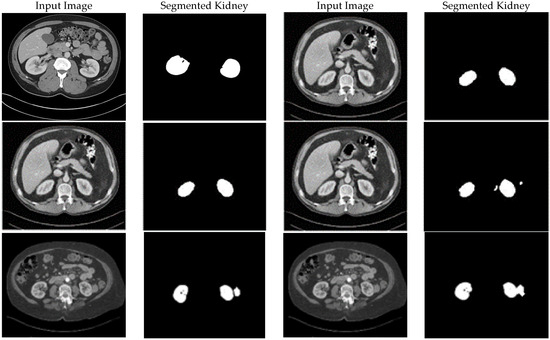

Enhancing Medical Image Segmentation and Classification Using a Fuzzy-Driven Method

Automated analysis for tumor segmentation and illness classification is hampered by the noise, low contrast, and ambiguity that are common in medical pictures. This work introduces a new 12-step fuzzy-based improvement pipeline that uses fuzzy entropy, fuzzy standard deviation, and histogram spread functions [...] Read more.

Automated analysis for tumor segmentation and illness classification is hampered by the noise, low contrast, and ambiguity that are common in medical pictures. This work introduces a new 12-step fuzzy-based improvement pipeline that uses fuzzy entropy, fuzzy standard deviation, and histogram spread functions to enhance picture quality in CT, MRI, and X-ray modalities. The pipeline produces three improved versions per dataset, lowering BRISQUE scores from 28.8 to 21.7 (KiTS19), 30.3 to 23.4 (BraTS2020), and 26.8 to 22.1 (Chest X-ray). It is tested on KiTS19 (CT) for kidney tumor segmentation, BraTS2020 (MRI) for brain tumor segmentation, and Chest X-ray Pneumonia for classification. A Concatenated CNN (CCNN) uses the improved datasets to achieve a Dice coefficient of 99.60% (KiTS19, +2.40% over baseline), segmentation accuracy of 0.983 (KiTS19) and 0.981 (BraTS2020) versus 0.959 and 0.943 (CLAHE), and classification accuracy of 0.974 (Chest X-ray) versus 0.917 (CLAHE). A classic CNN is trained on original and CLAHE-filtered datasets. These outcomes demonstrate how well the pipeline works to improve image quality and increase segmentation/classification accuracy, offering a foundation for clinical diagnostics that is both scalable and interpretable. Full article